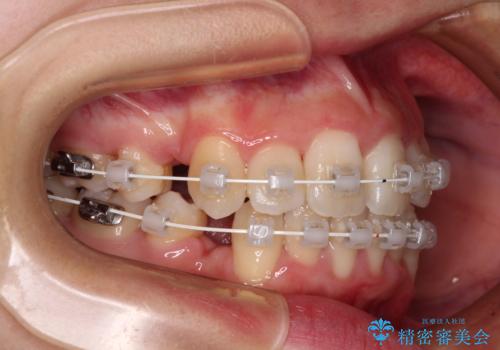

- 審美装置

- 2年3ヶ月

- 10-30回